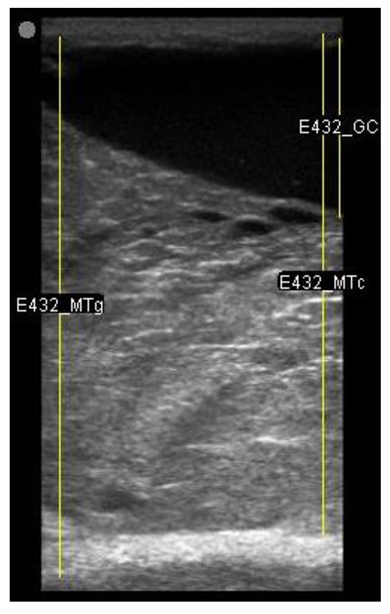

The image processing was undertaken using ImageJ software [28] as used by Abràmoff et al. [29]. The scales between pixels and millimetres were calculated based on the number of pixels, the scanning depth (mm), and the transducer width (mm) (Figure 4). This method relies on the ability of the operator to interpret and identify lines on the images. To standardize the assessment compartment depth, drawing templates were created for each time point as used by Molenaar et al. [30] and included four representative images from four different yearling ewes with and without the lines drawn for each compartment (Appendix A). The total depth of mammary gland conservative (MTc) was the smallest likely demarcation (abdominal wall) of the mammary gland (Figure 5a), and total depth of the mammary gland generous (MTg) was the largest likely demarcation of the mammary gland visible on the image [30] (Figure 5a). The MTc, MTg, fat pad (FP), parenchyma (PAR), and gland cistern (GC) depths were estimated at the deepest point for each sub-compartment, excluding the skin layers, using the straight tracer (Figure 5a) and were expressed in millimetres.

Figure 5.

(a) Demonstration of delimitations of the mammary total depth conservative (MTc) and generous (MTg), mammary gland cistern (GC), parenchyma (PAR) and the fat pad (FP) and (b) Demonstration of randomly positioning of regions of interest (1, 2, 3) in the parenchyma.